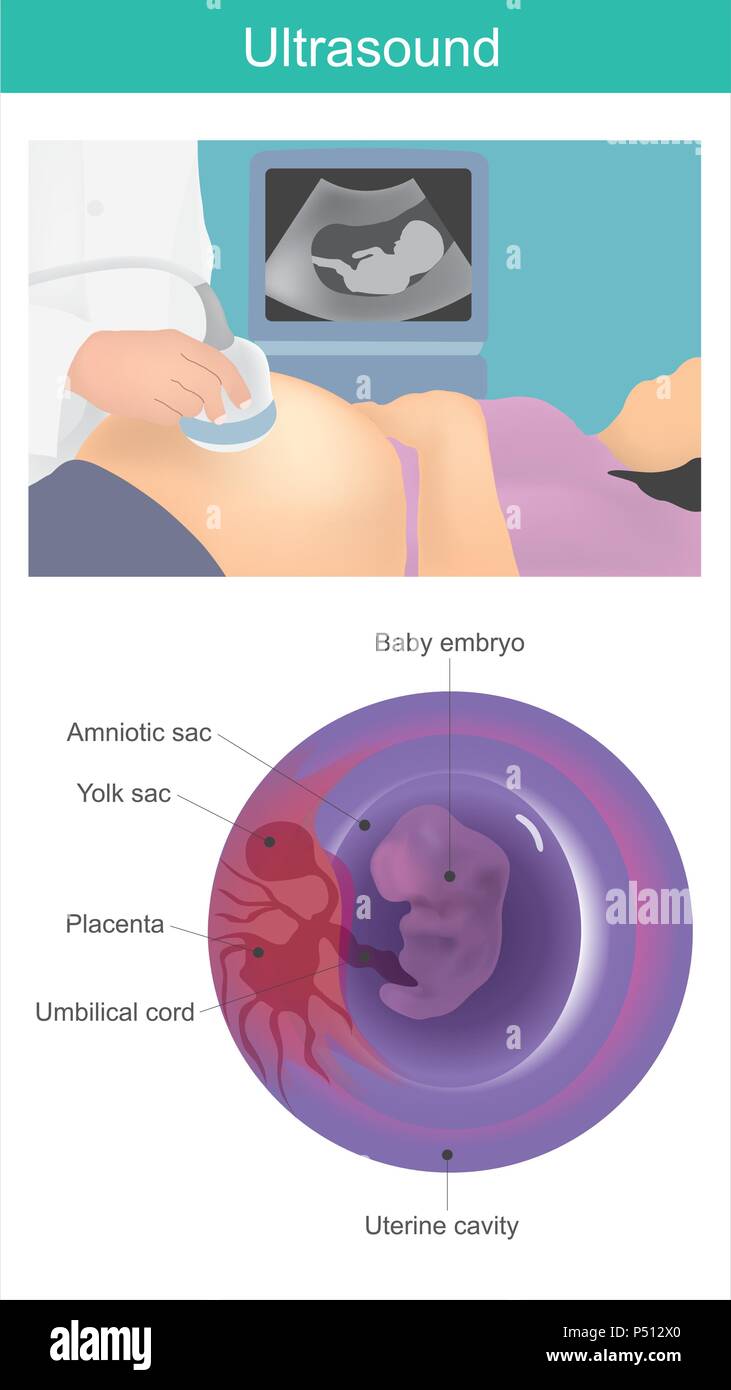

Bambino a ultrasuoni. Uso di onde acustiche per visualizzare l'embrione nella cavità uterina. Illustrazione Vettorialehttps://www.alamy.it/image-license-details/?v=1https://www.alamy.it/bambino-a-ultrasuoni-uso-di-onde-acustiche-per-visualizzare-l-embrione-nella-cavita-uterina-image209621944.html

Bambino a ultrasuoni. Uso di onde acustiche per visualizzare l'embrione nella cavità uterina. Illustrazione Vettorialehttps://www.alamy.it/image-license-details/?v=1https://www.alamy.it/bambino-a-ultrasuoni-uso-di-onde-acustiche-per-visualizzare-l-embrione-nella-cavita-uterina-image209621944.htmlRFP512X0–Bambino a ultrasuoni. Uso di onde acustiche per visualizzare l'embrione nella cavità uterina.